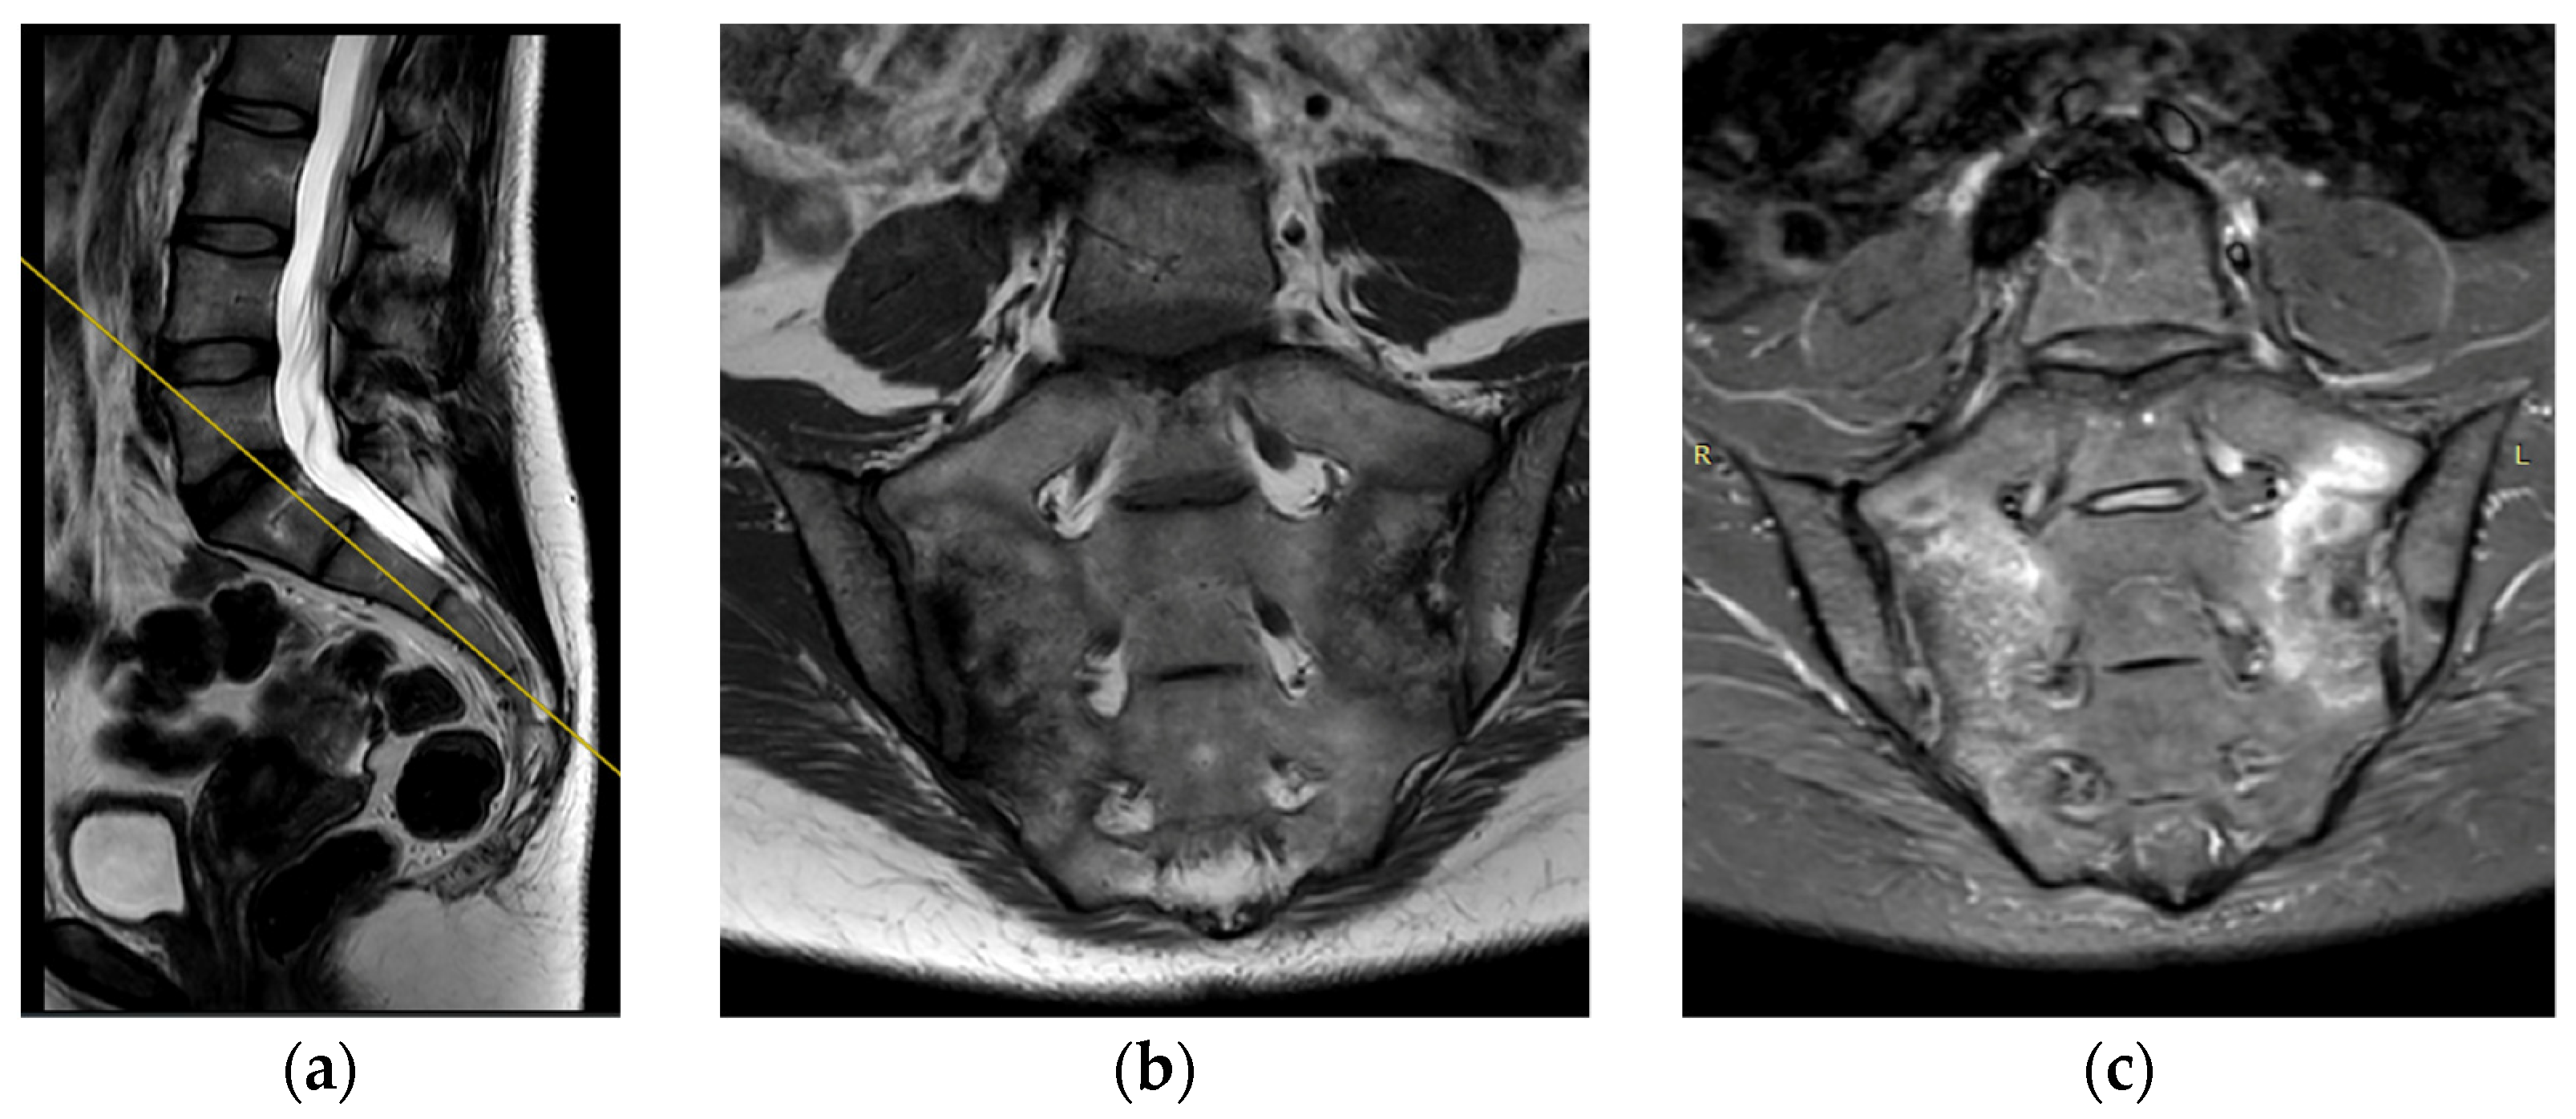

The deviation angles were measured on T2-weighted sequence slices obtained in the sagittal plane, as shown in Figure 1. Figure 2, presented below, shows the interrelationship of the three sequences of the same examination (as shown in Figure 1) that were used in this study. The RadiAnt DICOM Viewer was used to take measurements. All examinations were analyzed by two independent researchers in a blind study. The final results of the measurements were averaged to obtain a single deviation angle corresponding to each examination.

Figure 1.

The measured deviation angle equals 5.3 degrees (group 2). The red line is the fully correct line drawn between the posterior edges of the S1 and S2 vertebrae. The yellow line marks the actual plane in which the slices were acquired.

Figure 2.

(a) Example of sagittal T2 series. Yellow line indicates the position of coronal projections (b,c). (b) Example of coronal T2 series. (c) Example of coronal STIR series.